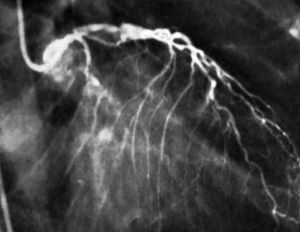

冠脈造影冠狀動脈造影是診斷冠心病的一種有效方法。將導管經大腿股動脈或其它周圍動脈插入,送至升主動脈,然後探尋左或右冠狀動脈口插入,注入造影劑,使冠狀動脈顯影。能較明確地揭示冠狀動脈的解剖畸形及其阻塞性病變的位置、程度與範圍。冠狀動脈造影是目前唯一能直接觀察冠狀動脈形態的論斷方法,醫學界號稱其為“金標準”。冠狀動脈造影術的死亡率約在0.11%-0.14%,心肌梗死率約在0%-0.06%;左冠狀動脈主幹病變患者的心肌梗死與死亡率均約在3.0%。

冠脈造影用於指導治療:對臨床上確認的冠心病患者,在內科保守治療不佳而考慮採用經皮冠狀動脈腔內成形術,(PTCA)、或主動脈-冠狀動脈旁路移植術時,必須先進行冠狀動脈及左心室造影,明確冠狀動脈狹窄的部位、程度及左心室的功能情況,以正確選擇適應症,制定治療方案。